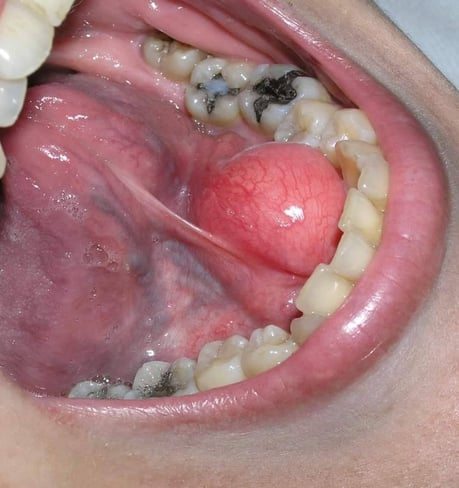

ガマ腫

粘液嚢胞

4.嚢胞(袋状になった病変)が親知らずの周りにでき、放置すると徐々に大きくなり、あごの骨が溶けてしまいます。